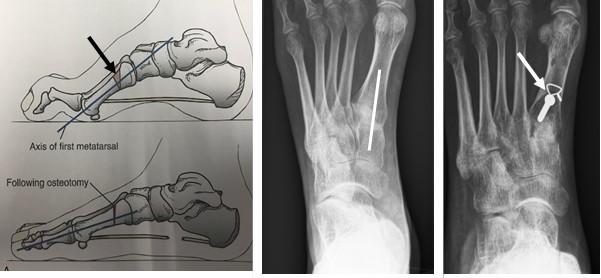

Calcaneus osteotomie

Bij een calcaneus osteotomie wordt het hielbot doorgezaagd en meer naar de buitenzijde verplaatst. De achtervoet komt zo meer van de “O” positie in een “X” positie.

Het vastzetten van beide botdelen gebeurt meestal met een schroef vanuit de hiel, middels een apart litteken.

Figuur 1: Voorbeeld van een calcaneus osteotomie. H=hielbot (calcaneus). De witte streep op het linker plaatje is de locatie van het litteken. De Rode pijl wijst naar de schroef. Op het meest rechtse plaatje zie je de verschuiving van het hielbot naar de buitenzijde